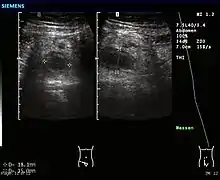

Ultrasound

Abdominal ultrasonography, preferably with doppler sonography, is useful to detect appendicitis, especially in children. Ultrasound can show the free fluid collection in the right iliac fossa, along with a visible appendix with increased blood flow when using color Doppler, and noncompressibility of the appendix, as it is essentially walled-off abscess. Other secondary sonographic signs of acute appendicitis include the presence of echogenic mesenteric fat surrounding the appendix and the acoustic shadowing of an appendicolith.[46] In some cases (approximately 5%),[47] ultrasonography of the iliac fossa does not reveal any abnormalities despite the presence of appendicitis. This false-negative finding is especially true of early appendicitis before the appendix has become significantly distended. Also, false-negative findings are more common in adults where larger amounts of fat and bowel gas make visualizing the appendix technically difficult. Despite these limitations, sonographic imaging with experienced hands can often distinguish between appendicitis and other diseases with similar symptoms. Some of these conditions include inflammation of lymph nodes near the appendix or pain originating from other pelvic organs such as the ovaries or Fallopian tubes. Ultrasounds may be either done by the radiology department or by the emergency physician.[48]